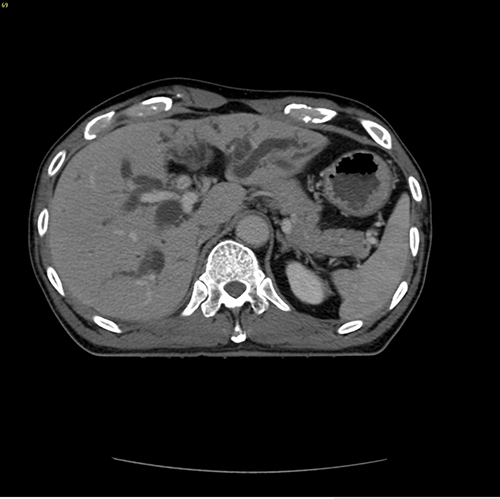

IV型胆管癌---胆管癌根治(左半肝+尾状叶切除)